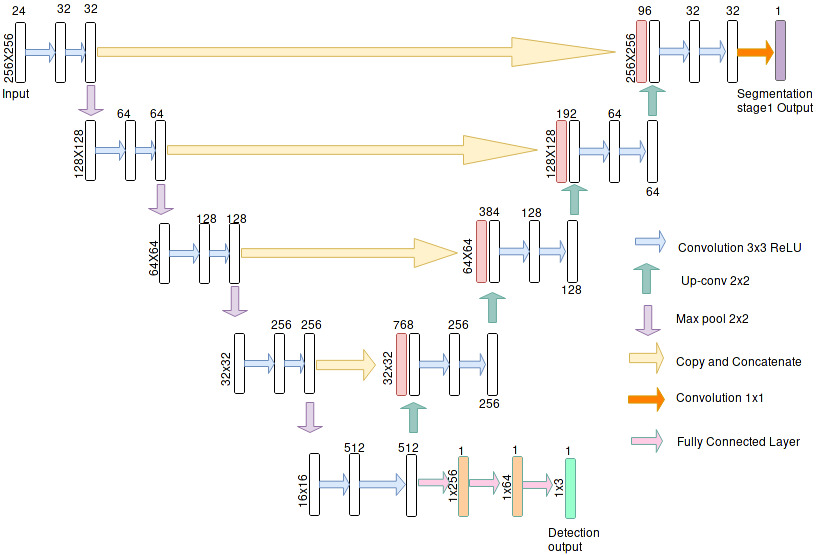

A CNN is generally used in computer vision tasks for solving classification and segmentation tasks. In this work we propose to use a CNN architecture to learn the function that will combine the ensemble of GMP images. The learned function will effectively map the ensemble of GMP images into an output image predicting the retinal fluids. The design of the architecture for this problem is based on a cascade of Fully Convolutional Networks consisting of two independent networks joined in an end to end form to perform joint segmentation and detection. Both the independent networks here are similar to the widely used U-net FCN architecture[10]. The description of the network is shown in the Fig. 2.

The output of the first stage of the cascaded FCN is a map representing probable retinal fluid regions. The thresholded output of this map forms the retinal fluid prediction mask. GMP creates a smearing effect resulting in suppressing the edges of abnormalities with very less volume. To overcome this we provide the original image along with the predicted map as the input for the next stage of the cascaded network. The final FCN generates three masks for each type of retinal fluid as its output. The detection subtask is handled by introducing a fully connected layers at the end of first cascaded stage. The predication at individual slice level for each type of retinal fluid is combined to produce a prediction for the entire volume as mentioned in section 2.3.